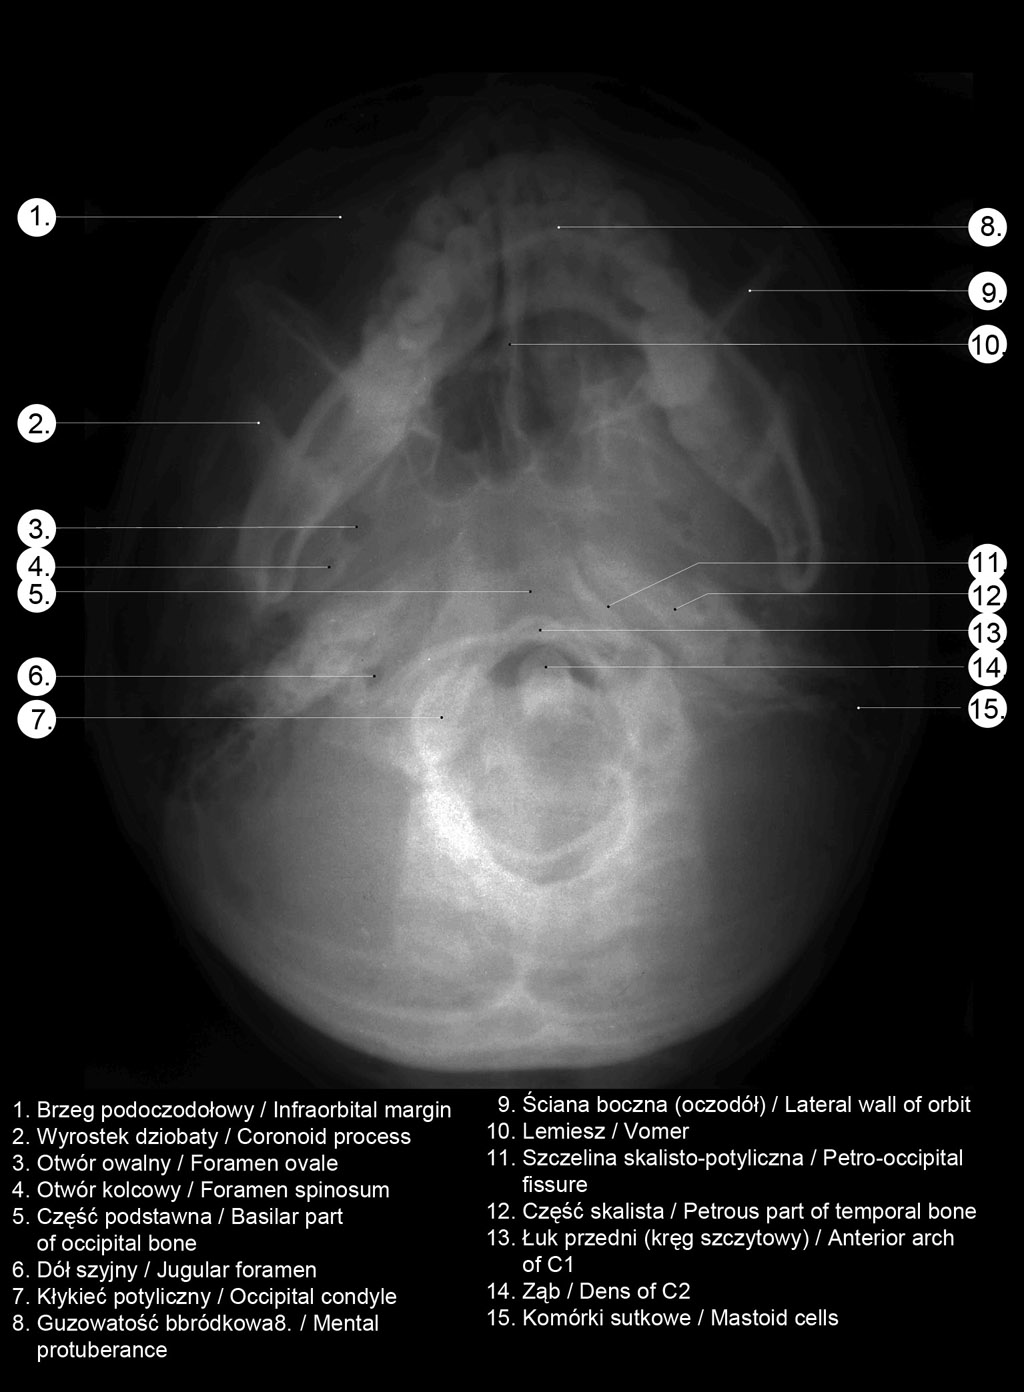

Radiografia / Radiography

RTG głowy od góry.

. RTG głowy człowieka.